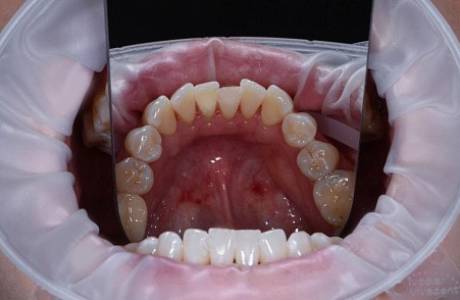

До лечения

Налет и зубной камень на нижней челюсти